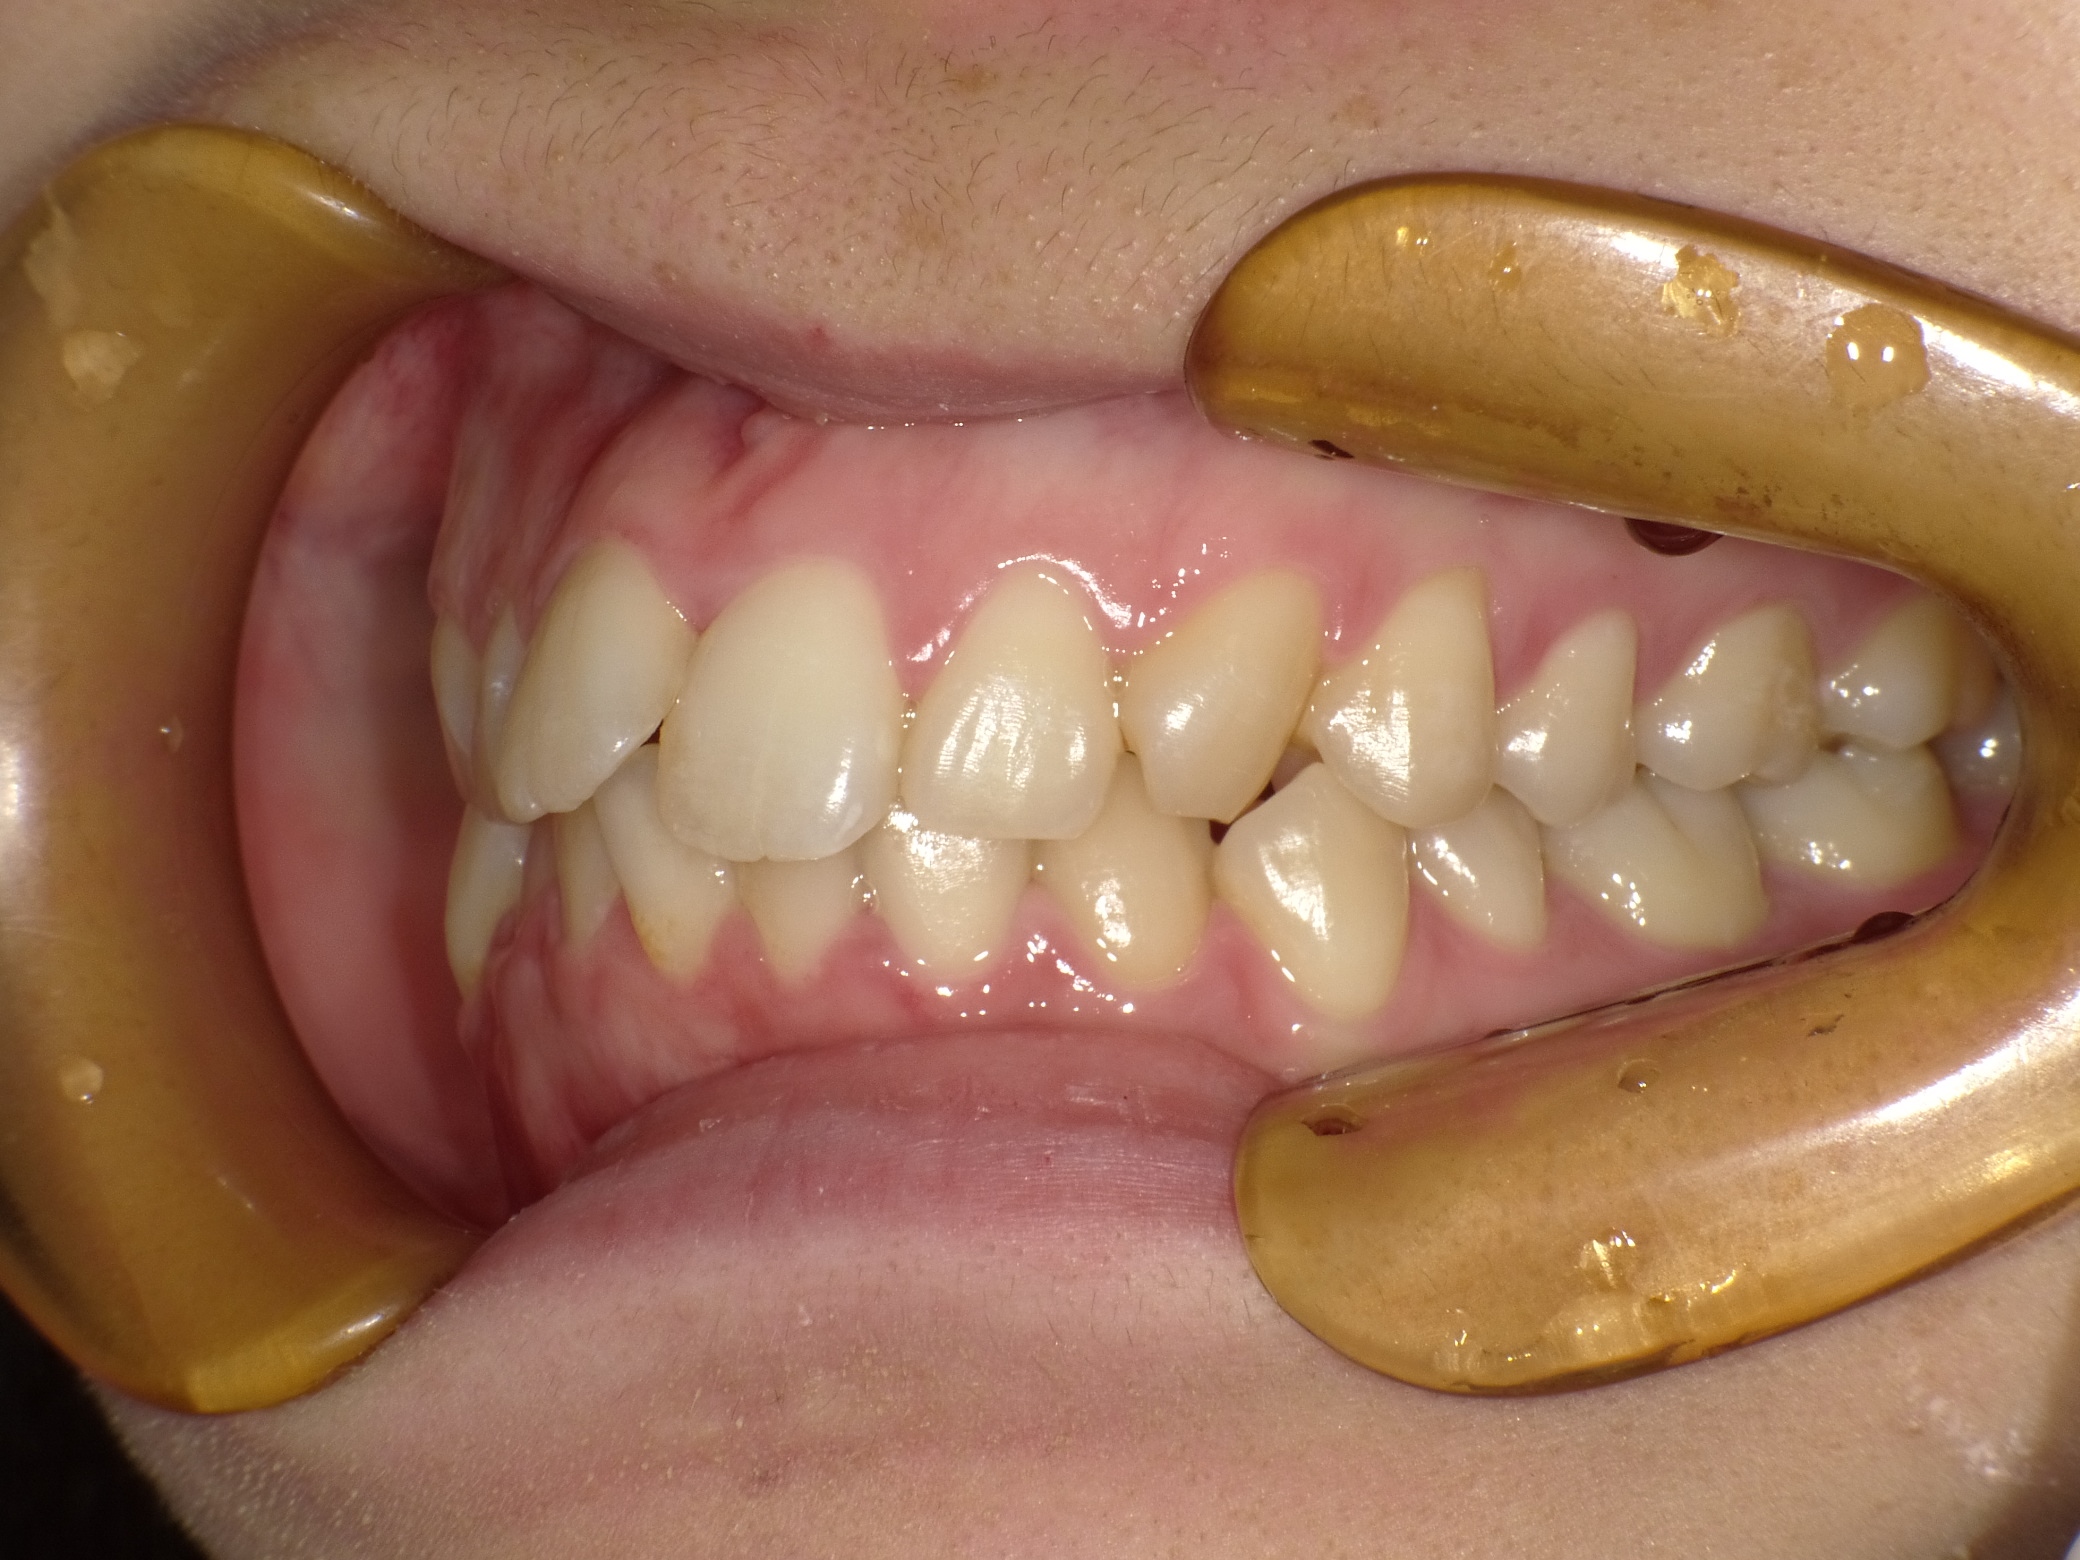

口内左

治療前

治療後